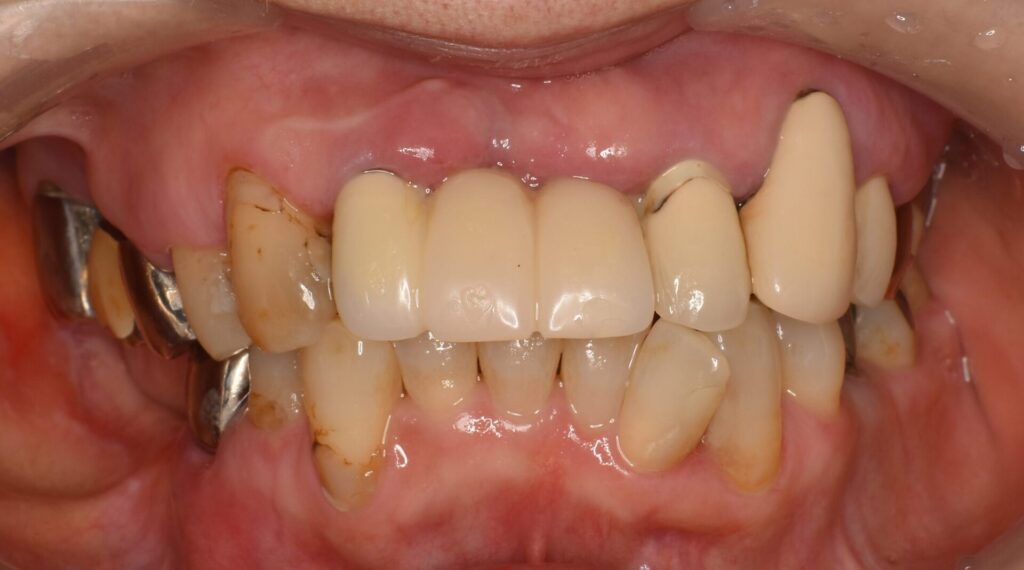

Before

| 主訴 | ・左上奥のブリッジと前歯がグラついて食事できない。 ・右下に入れ歯が入っているが痛くて使えていない。 ・全体的にキレイにしたい。 |

| 診断名 | ・二次虫歯(重度根尖性歯周炎) |

| 治療方法 | ・左上の奥歯と前歯は残せなかったため抜歯をしインプラント手術を行い、治癒を待つ間に仮の歯を入れて噛める状態にしてから右下の奥歯のインプラント手術を行いました。 その後、インプラントと骨がしっかりと結合したことを確認し、ジルコニアボンドを被せる治療を行っています。 ・右上は根がしっかりしていたので、根の治療からやり直し、ジルコニアボンドのブリッジを入れました。 |